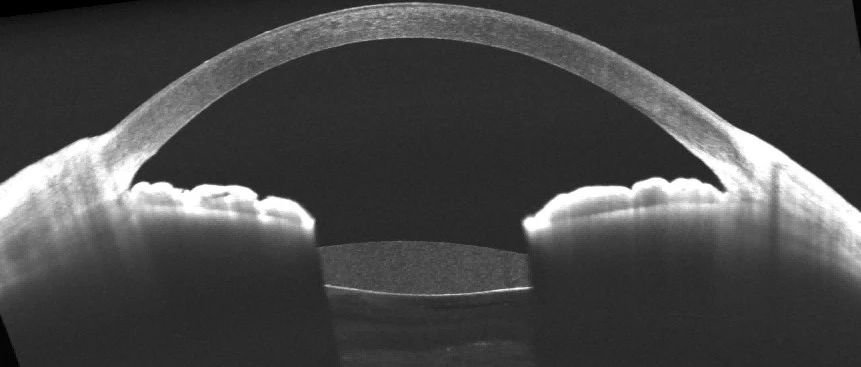

超乳玻切术后即时与延期人工晶状体植入有无偏斜差异?近期,上海爱尔眼科医院李轻宸博士,上海嘉定区中心医院眼科杨舟医生和上海市中医医院眼科刘瑞医生,运用图湃全域扫频OCT的另一款系列——瑶光·星,进行眼前节的OCT图像采集。在《Indian Journal of Ophthalmology》刊登标题为《Intraocular lens tilt and decentration after primary and delayed implantation in phacovitrectomy for maculaoff rhegmatogenous retinal detachment repai...